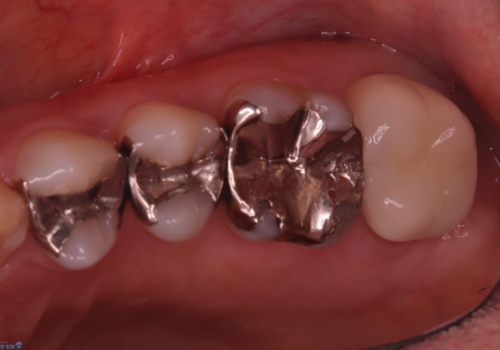

保険適用のメタルインレーと歯質の境目にう窩ができており、補綴物のやり替えとなりなした。

メタルインレーを除去したところう窩が深く、遠心の健歯質が歯肉縁下深くに位置したためディスタルウェッジ術を行い骨と歯肉の高さを下げた上で補綴しています。

元々インレーが入っていましたが、残存歯質量が少なく破折のリスクを説明しジルコニアクラウンでのやり替えとなりました。